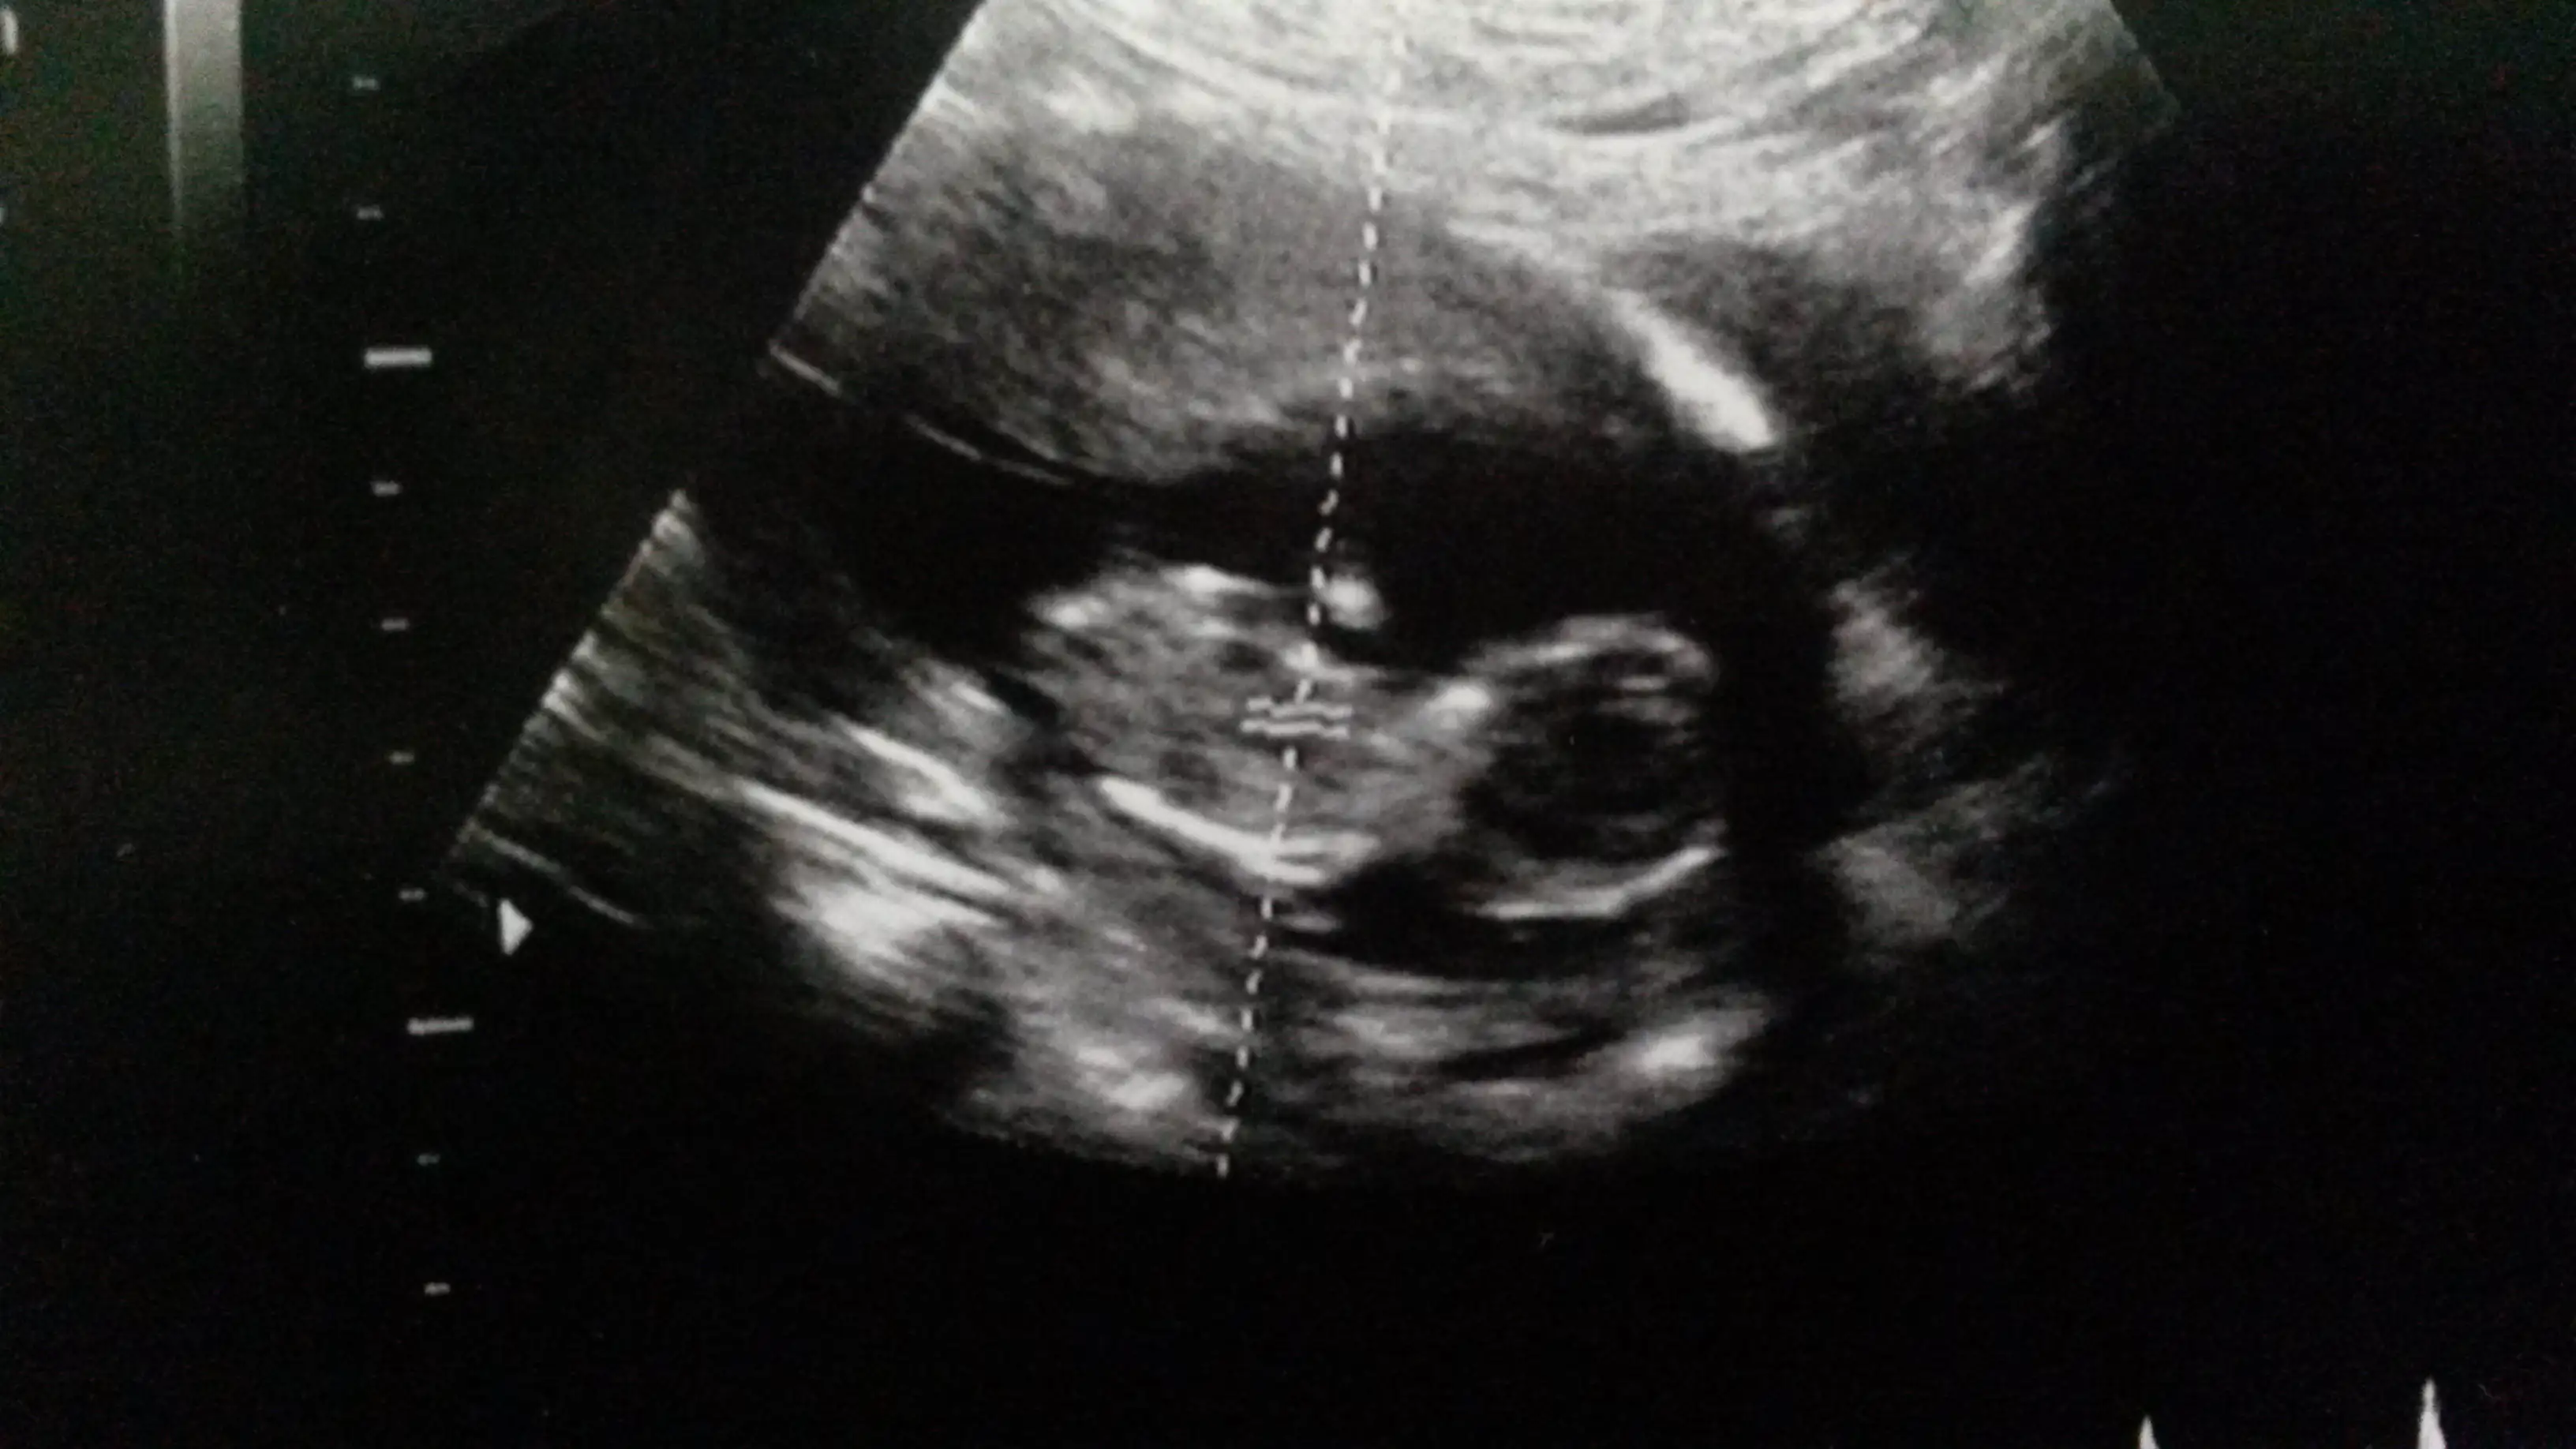

Hayirli olsun canim saglikli olsunda pipisinide kukusunada raziyiz:)Suanki durumuna gore erkek dedi cnm ikili testini yaptirdik cok sukur sorun cikmadi cikintisinida yani pipisinide gosterdi ilerleyen haftalarda tam netlesir dedi :)

Aynen canim hatta ben ense kalinligi ve burun kemik olcumu felan iyi ciktigina cinsiyetinden daha cok sevindim oncelikle saglikli olsun tabiki :)Hayirli olsun canim saglikli olsunda pipisinide kukusunada raziyiz:)

Anladim cnm bizde 12 haftlalik diye ikili teste gittik bir hafta onden gidiyormus bakti cinsiyetine erkege benziyor dedi sonra detayli alt tarafina bakti bebek uyuyordu zorla uyandirdik sonra saga sola donmeye basladi ultrasonu o yuzden tam net cekemedi boyunu bile zor olctuk :) ama pipisini gosterdi hafiften cikintisi belirginlesmis cok komikti hali ama parmak kadar bebek ama insan gibi herseyi var :)Denizkizi esra eğer demeseydn erkek diye ben yine kiz derdim nubunu hala paralel görüyorum sen netlestigindede haber ver bize gerçi pipi gostermisse dogrudur